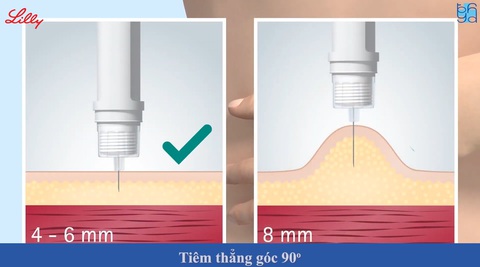

Véo da để dễ dàng cố định vị trí tiêm

Đâm kim thẳng góc 90 độ qua da tại vị trí tiêm

Ấn nút tiêm hướng xuống đến khi vạch chỉ liều tiêm trở về số 0

Giữ nguyên kim và đếm 10 giây mới rút kim ra

Đâm kim thẳng góc 90 độ qua da tại vị trí tiêm